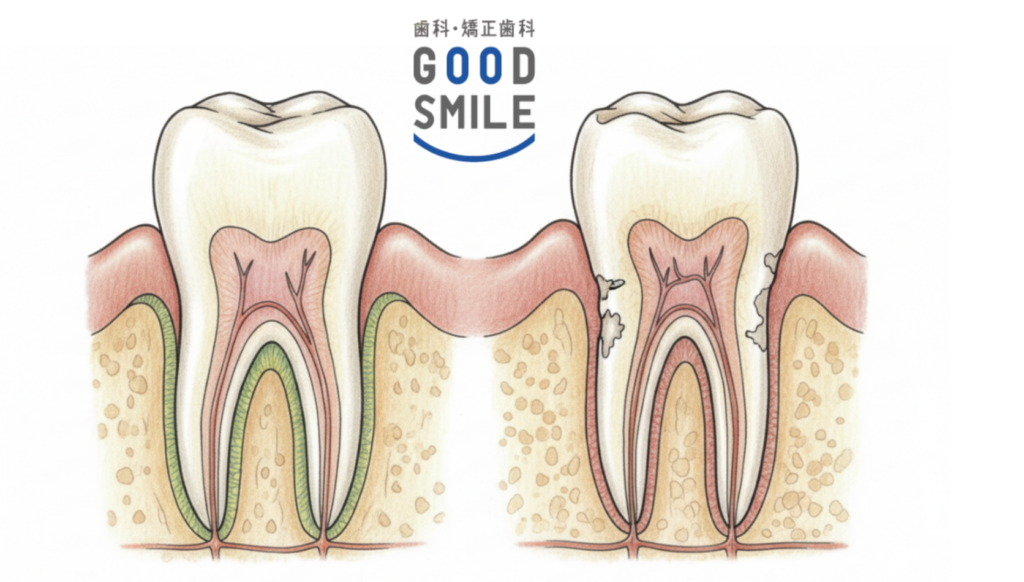

歯根吸収とは、歯の根の部分が少しずつ溶けて短くなったり細くなったりする現象のこと。矯正治療では歯に力をかけて移動させますが、その過程で歯の周囲の骨が作り替えられます。歯が動く方向の骨は一旦溶けて無くなり、反対側では新しい骨が作られる……この「骨の吸収と添加」が繰り返されることで歯が動いていくのです。

本来は骨だけが吸収されるはずですが、まれに歯根までもが吸収されてしまうことがあります。

患者さん個人の要因としては、「元々の歯根の形態」が大きく関係します。もともと歯根が短い、細い、先端が尖っているといった形状の場合、歯根吸収が起こりやすい傾向があるのです。

どの歯に起こりやすいかという点では、上顎の前歯が最も歯根吸収が生じやすく、次いで下顎の前歯、下顎第一大臼歯の順となっています。